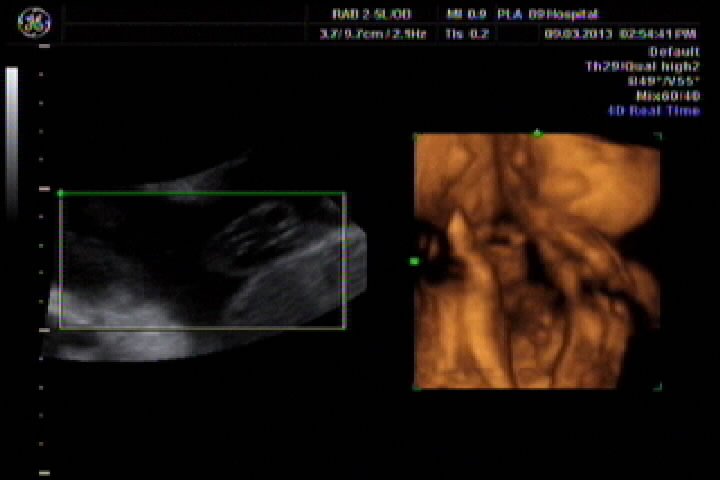

今天刚做了四维彩超,刻了光盘,但不会看,想请专业认识帮我看看胎儿性别,胎儿27周又5天 点击展开 匿名用户 2013-03-10 00:01 为您推荐: 其他回答 你这个大夫估计就是骗你钱呢,打的什么图像,宝宝一点没照到,而且图像特别虚,上面的图片只是羊水和脐动脉,一点实质性内容都没有 宫和玉_XzIQ 2013-03-10 10:16 汗。。。 说了违法。 而且网上的人说了你就信啊。 忽悠你不要钱的。 孟觅翠_RspR 2013-03-10 00:19 相关问题 孕晚期如何测胎儿性别怎样从四维彩超数据看胎儿性别? 多久怀孕可以判断胎儿性别,怎么判断我现在孕7周 14周B超数据如何来判断胎儿性别 前壁,双顶径27,股骨长13,能看出男孩女孩吗?